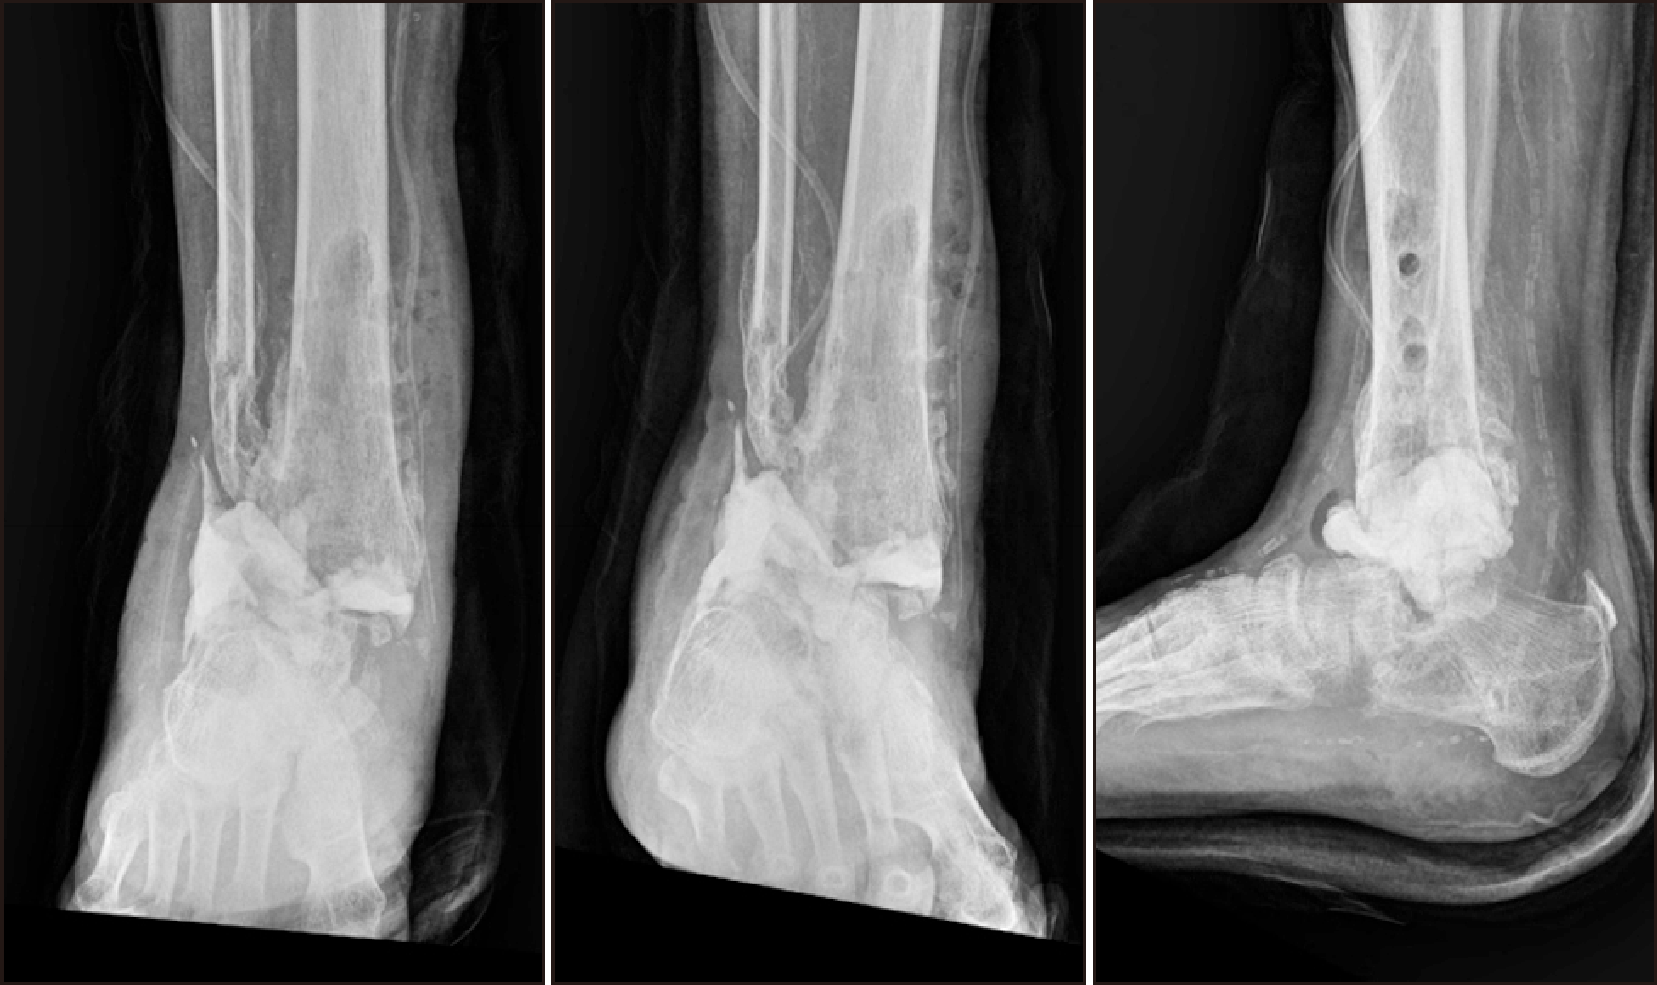

Subsequent imaging studies revealed non-union and lateral displacement of the fractures, prompting a revision OR/IF. The patient was also placed in isolation due to COVID-19, and further radiographs revealed metal failure and tibiotalar joint dislocation (Fig. 5). An implant-associated infection was confirmed, leading to subsequent procedures including metal removal, debridement, and the application of an external fixator (Fig. 6).

Figure 5

(A) Five weeks post-surgery, radiograph confirming non-union and lateral displacement of the fractures. (B) Findings of metal failure and tibiotalar joint dislocation observed during COVID-19 isolation.

Figure 6

(A) Post-operative radiograph after applying external fixator for septic ankle findings. (B) Intra-operative clinical picture applying external fixator for septic ankle findings.